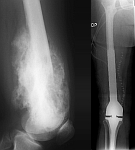

- Resection of benign and malignant tumors of the bone and soft tissue

- Tumor total endoprosthesis (TEP) of all large joints and bones